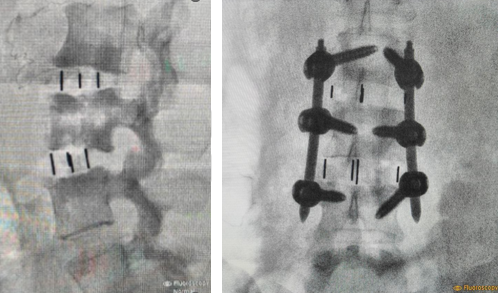

After Surgery Results

Posterolateral Fusion – fusion at the back of the spine without removing the disc, typically used when the front of the spine is stable.

The surgeon removes the damaged disc or diseased bone, places a cage or bone graft between the vertebrae, and secures it with screws and rods. Over months, the bones heal together naturally. The surgical approach (front, back, or side) depends on the patient's specific condition and body type.